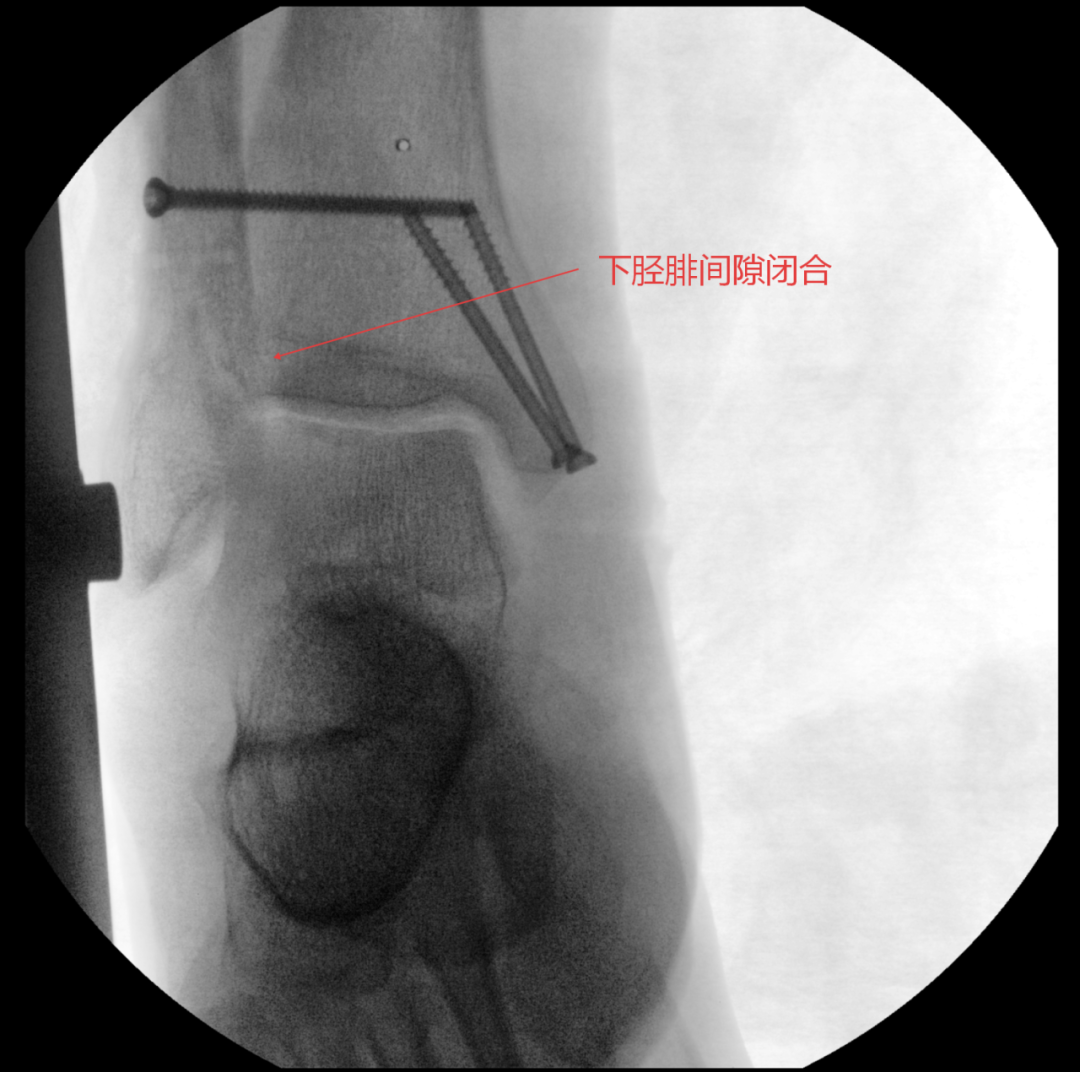

随后,医疗团队为王大爷开展手术治疗。

术中进行下胫腓拉力试验结果呈明显阳性,且复位效果未达预期,团队当机立断决定切开探查,发现前结节骨折块嵌顿于下胫腓间隙,正是阻碍复位的关键,取出骨折块后顺利完成复位,手术按规范流程顺利结束。

术后,王大爷接受了系统化的规范护理与康复指导,踝关节的肿胀、疼痛逐步缓解,目前已能逐步恢复正常行走。